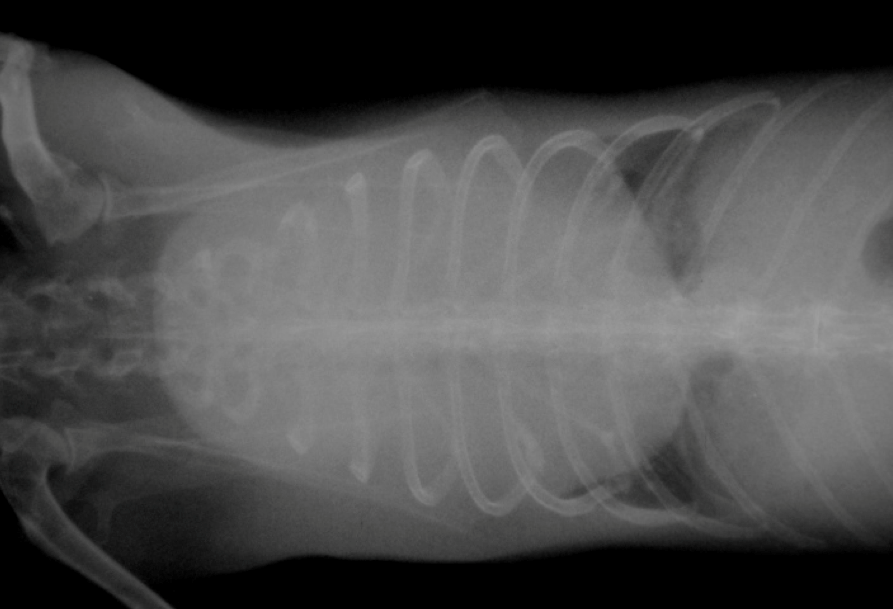

3. التيموما وأورام الغدة الزعترية (Thymoma / Thymic Lymphoma)

- من أكثر الكتل المنصفية شيوعًا في الأرانب.

- العرض الكلاسيكي: جحوظ عيون (Exophthalmos) مؤقت أو دائم بسبب اضطراب العود الوريدي من الرأس.

- يجب إجراء تصوير صدري لكل أرنب يظهر عليه جحوظ العين لاستبعاد الكتلة المنصفية.

(تُظهر هذه الصورة الشعاعية لصدر أرنب تأثيرًا كتليًا ملحوظًا في منطقة المنصف الأمامي. يُعد هذا مظهرًا شائعًا لورم الغدة الزعترية أو ورم الغدد اللمفاوية الزعترية. يلزم إجراء خزعة للتمييز بين الحالتين.)

العلاج

- الجراحة قد تنجح في حالات التيموما إذا كان قابلاً للاستئصال.

- في حالات الليمفوما المنصفية يكون الاستئصال أصعب.

- المعالجة الإشعاعية للصدر أثبتت نجاحًا في بعض الحالات مع بقاء الأرانب سنوات بعدها.

- في الحالات غير القابلة للعلاج المتقدم يمكن استخدام البريدنيزولون فمويًا كعلاج تلطيفي.